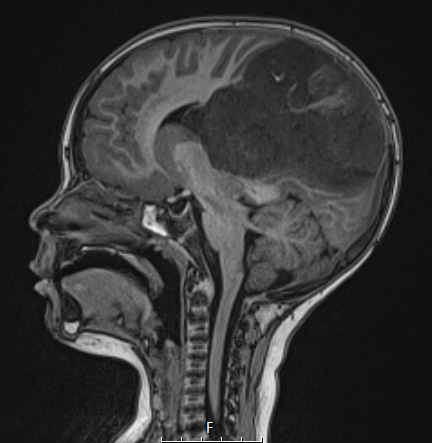

1A2,3 A T1-weighted scan without contrast image confirms the size and mass effect on the surrounding brain as shown in sagittal (1A2) and axial (1A3) scans.